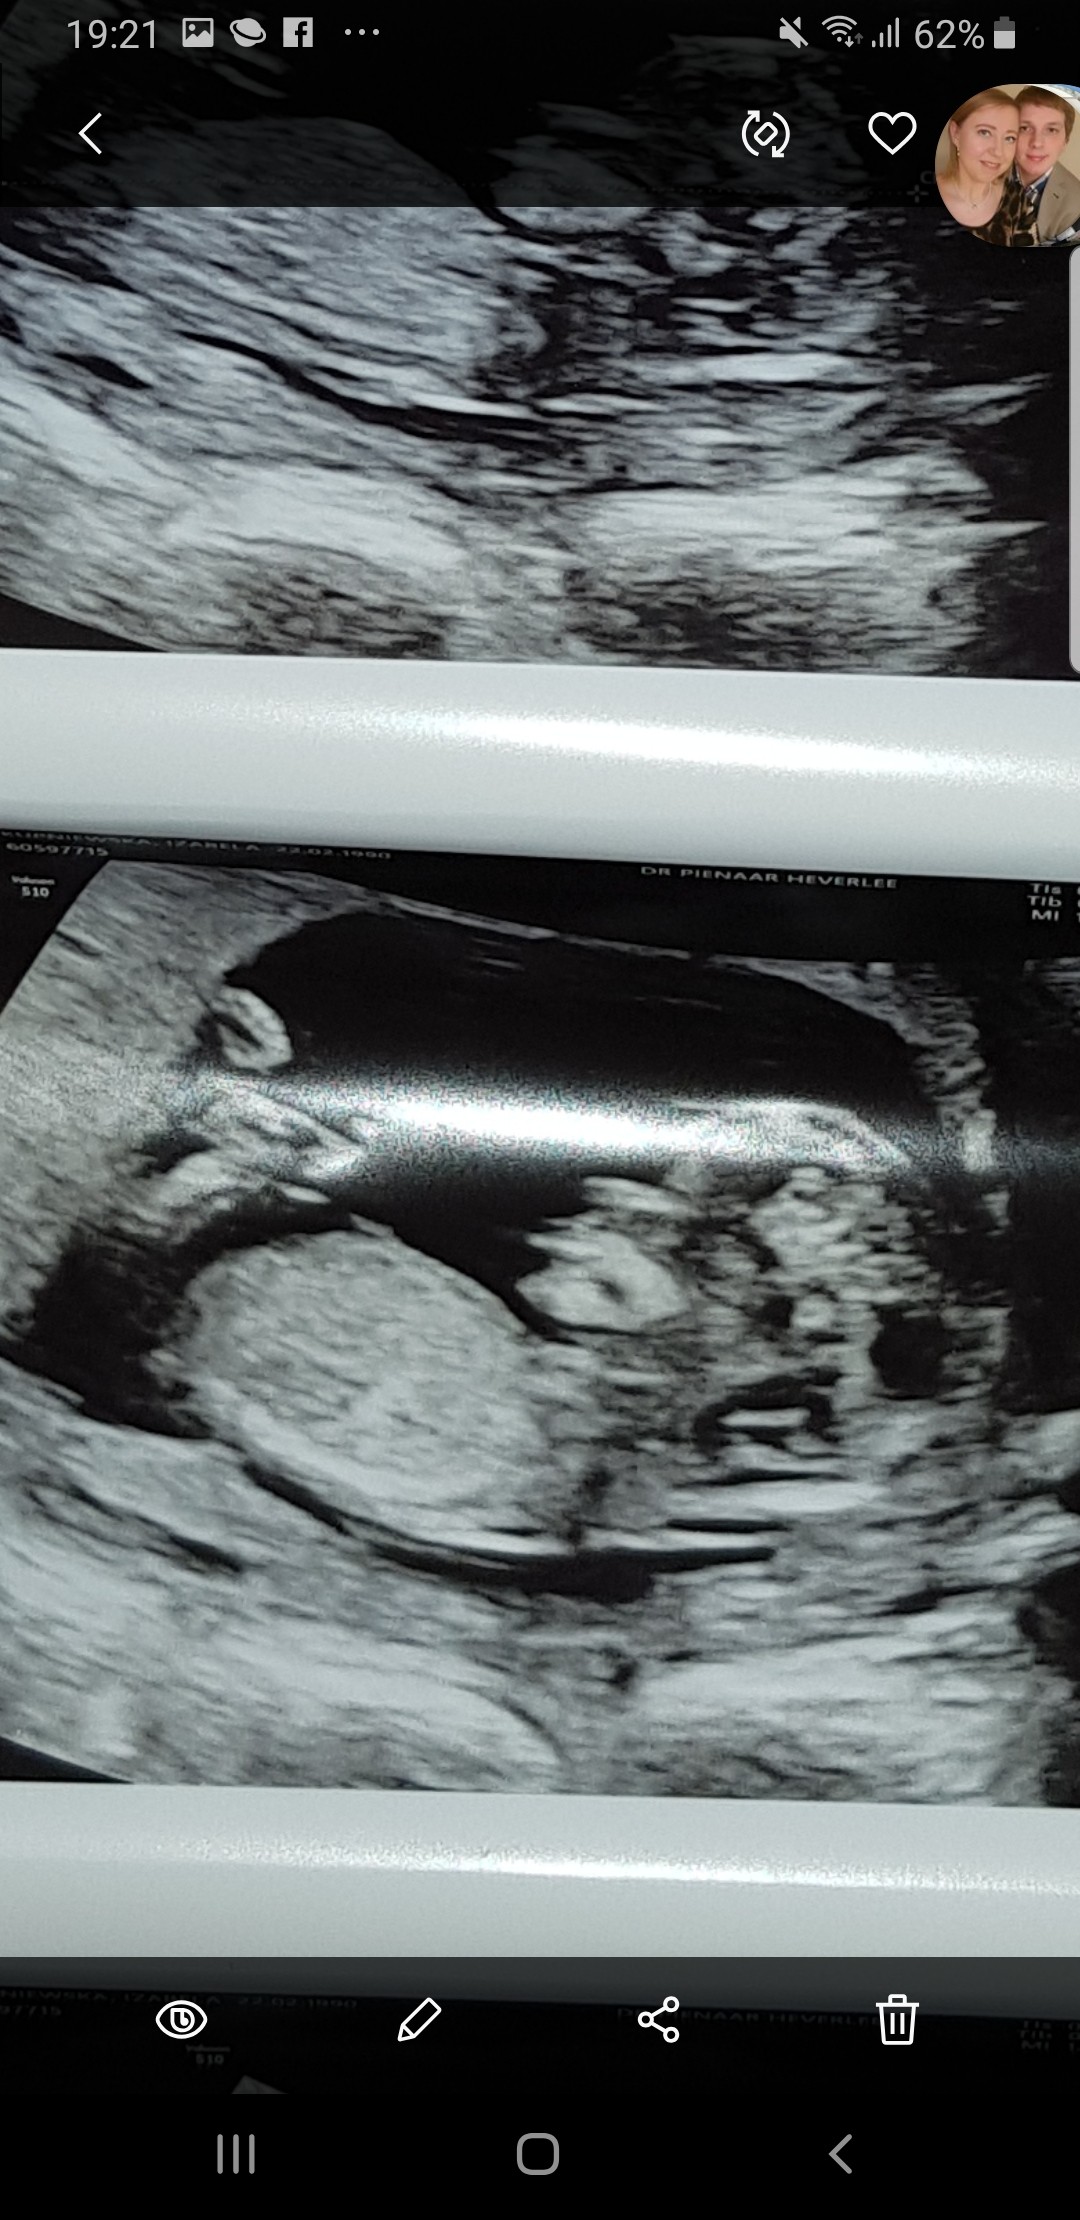

Plec z usg

Zdjecie w zalaczniku. Usg 13sty tydzien. Na moje nie widac tu zadnego wyrostka- jak to mowliwe???Czy w takim razie to dziewczynka? Lekarz sie nic nie chcial wpowiedziec :( Pomozcie dziewczyny specjalistki :*

Na szczescie musze tylko do wtorku czekac na wynik badania NIPT, wiec tylko tydzien od tego usg, ale i tak juz bym chciala wiedziec :P Czas sie jakby zatrzymal ha ha ha Wiem, straszna jestem :-) I jak neta i fora przegladam to juz te wyrostki widac i to nawet dokladnie w takim wieku ciazy.